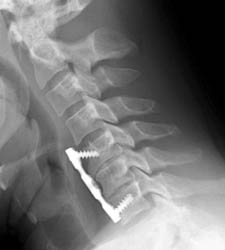

40 year old. male with history of falling off a truck while doing some work had complained of low back pain, muscle spasm, hand and feet numbness, and neck pain since the time of the action. Patient underwent C5-6 and C6-7 anterior cervical discectomy with fusion using anterior plating.

Lateral c-spine -Clik on the image to enlarge Lateral radiograph taken six weeks later on routine follow-up demonstrates loosening of the  superior anterior screws and ventral displacement of the proximal anterior plate. Early incorporation of grafting material can be seen at the disc spaces.